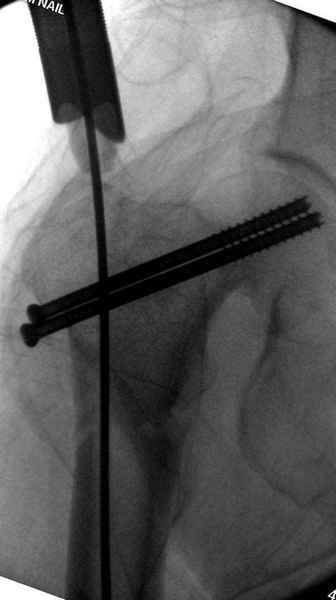

Профилактику дальнейшего раскола неполного перелома шейки провели тремя канюлированными шурупами.

На второй день после выписки упал дома. Снимки приложены. Коллеги рекомендуют удаление шурупа и вытяжение. Что делать?

Правильно, ситуация изменилась, как говорят у нас теперь "different animal", надо решать проблему подвертельного перелома. При наличии различных вариантов фиксаторов, включая Страйкер Гамма 3, мы выбрали DePuy Antegrade Trachanteric Nail из-за многовариантности проксимальной фиксации и двойного изгиба. Вводится через вертел под 8 градусным углом, и есть достаточный передний диафизарный изгиб, предупреждающий пенетрацию дистального переднего кортекса.